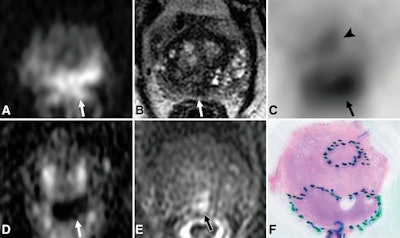

Overall, Ga-68 PSMA-11 PET/MRI depicted prostate cancer in 31 patients (97%), compared with 79% with multiparametric MRI (23 of 29 patients with conclusive multiparametric MRI examinations).

The histopathologic exams detected 412 positive tumor regions (43%) among 960 total regions in the 32 patients. By comparison, Ga-68 PSMA-11 PET/MRI depicted a few more positive tumor regions -- 434 regions (45%) -- while multiparametric MRI found 287 positive regions (30%).

In assessing the raw stringent and alternative neighboring approaches, Ga-68 PSMA-11 PET/MRI significantly exceeded multiparametric MRI for sensitivity in both cases (p < 0.001). As for specificity, Ga-68 PSMA-11 PET/MRI was significantly less than multiparametric MRI with the raw stringent approach but similar with the alternative neighboring approach (p = 0.99).